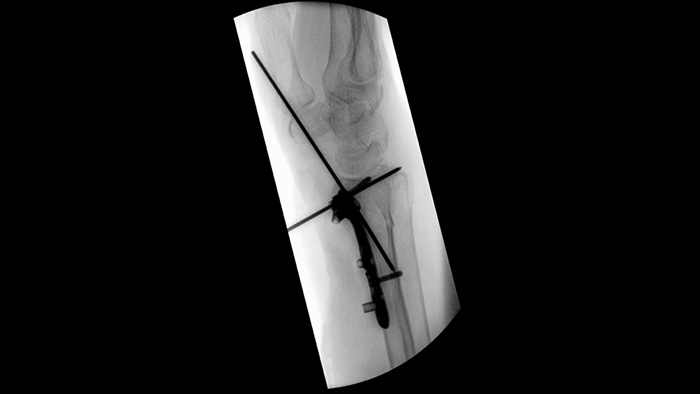

Beim Einsetzen von Pedikelschrauben für eine Spondylodese oder die Behandlung einer Fraktur sind vollste Konzentration und Teamarbeit gefragt. Laut einer Anwenderstudie ermöglichen die Navigationshilfen des Unify Workflows reibungslosere Interaktionen und weniger Abstimmungsfehler bei chirurgischen Teams.1

Position Memory vereinfacht den Arbeitsablauf bei komplexen orthopädischen Verfahren, bei denen der mobile C-Bogen häufig neu positioniert werden muss. Mit Position Memory2 erzielten die Teilnehmer einer Anwenderstudie1 94 % auf Anhieb richtige Neupositionierungen und erlebten weniger Frustration bei (Neu-)Positionierungen.